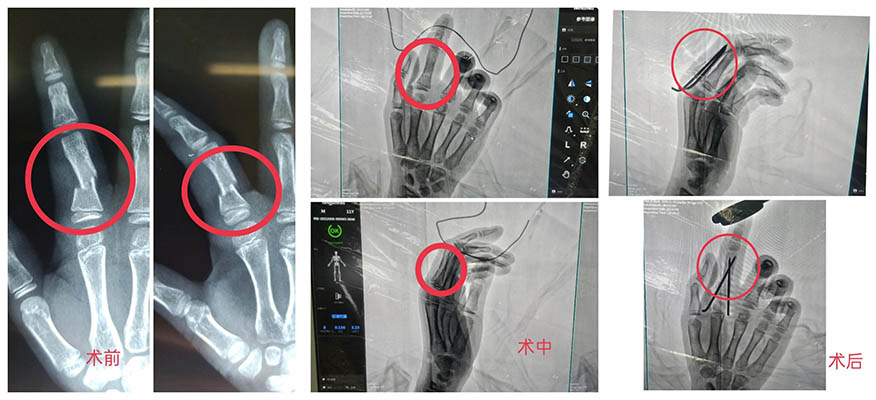

【案例分享】小孩手指砸傷骨折!我院創(chuàng)傷外科順利實(shí)施骨折復(fù)位手術(shù)

近日,濰坊市市立醫(yī)院創(chuàng)傷外科為一位11歲小朋友實(shí)施了右手示指近節(jié)指骨閉合復(fù)位克氏針內(nèi)固定術(shù)及石膏外固定術(shù),幫助小患者手指骨折部位成功復(fù)位。

骨折部位手術(shù)前后對(duì)比

經(jīng)拍片檢查發(fā)現(xiàn),小朋友的右手示指近節(jié)指骨骨折。經(jīng)過(guò)精密的術(shù)前準(zhǔn)備,創(chuàng)傷外科孫守全主任在麻醉團(tuán)隊(duì)的配合下,為小朋友行右手示指近節(jié)指骨閉合復(fù)位克氏針內(nèi)固定術(shù)及石膏外固定術(shù)。手術(shù)出血少、創(chuàng)傷小,骨折部位成功復(fù)位。